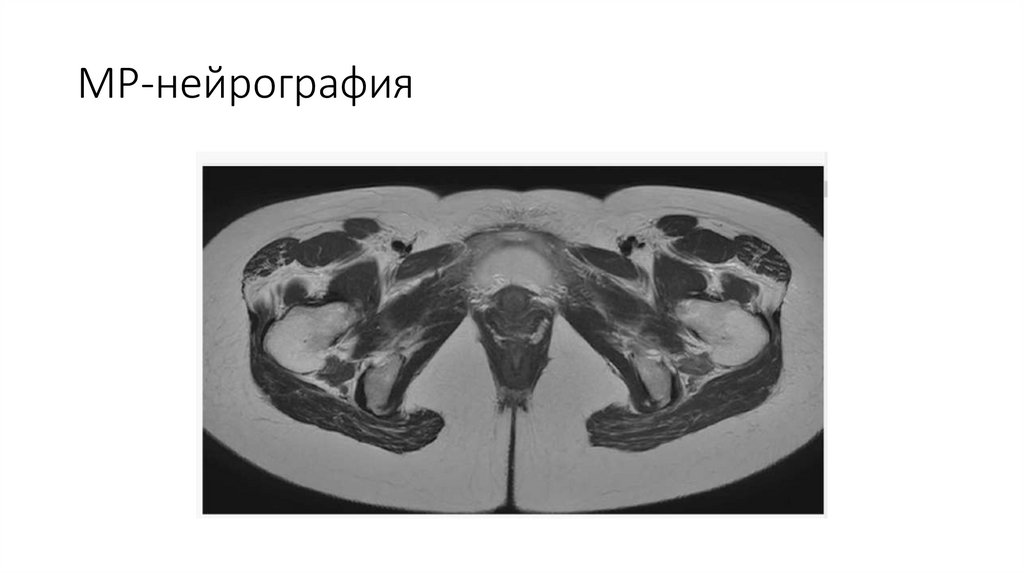

7. МР-нейрография

8. Режимы

9.